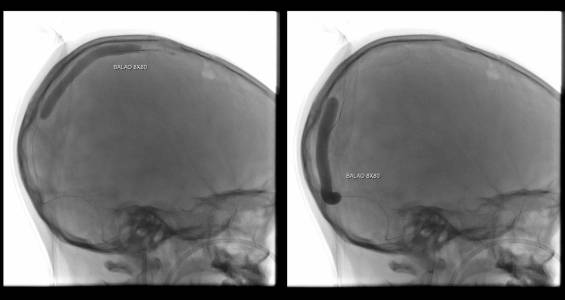

Foi realizada discussão entre as diversas especialidades, em vista da não melhora com o uso do anticoagulante, foi sugerido a tentativa de trombectomia mecânica do seio dural.

O caso clínico apresenta a utilização de materiais com finalidades primárias para trombectomia mecânica no contexto de acidente vascular cerebral (Rebar 27 + Solitaire) e o balão Copernic RC (Balt) comumente utilizado auxiliando na embolização de fístulas durais para os seios, auxiliando no processo de trombectomia mecânica no contexto de extensa trombose venosa cerebral.